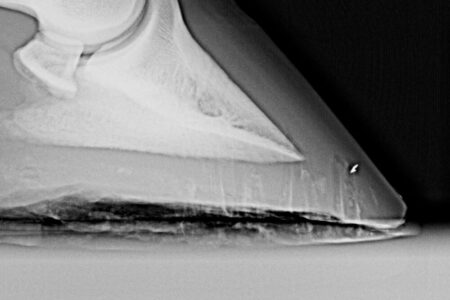

Ringbone in Horses

You can help the horse with ringbone with lifestyle changes, supplements, pain medications, and surgical options. It is a degenerative disease, and some ringbone in horses is mild, while other cases more severe.